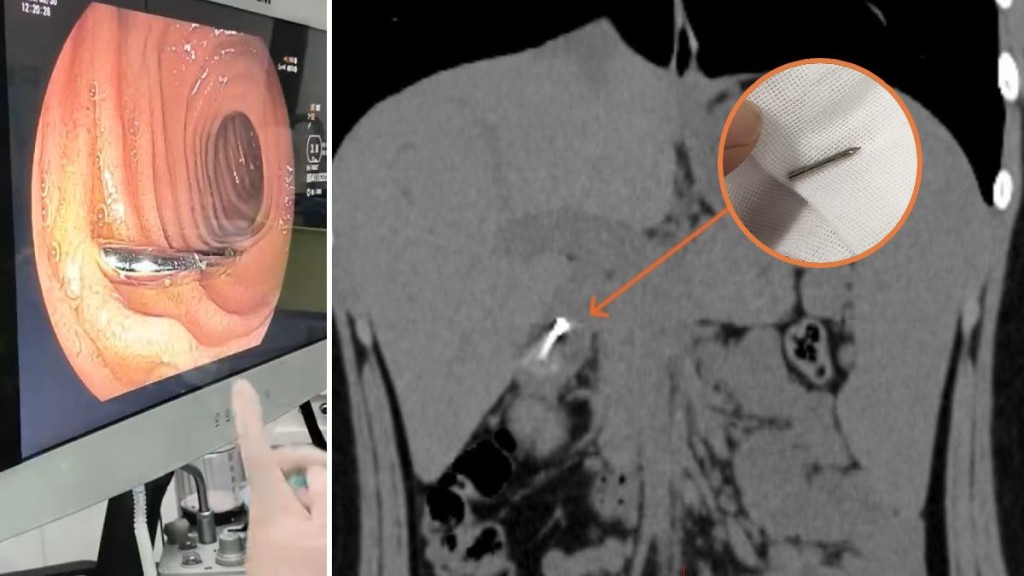

- 電腦掃描顯示,針狀異物已到達胃部與十二指腸之間,有刺穿消化道風險。

經電腦掃描檢查,發現針狀異物已到達胃部與十二指腸之間。由於針尖鋒利,隨時可能刺穿消化道,引發腹膜炎。手術面臨兩大挑戰:一是患者胃內仍有大量未消化食物,按規定進行全身麻醉內窺鏡手術需禁食至少六小時;二是患者年紀尚輕,胃部發育未全,麻醉期間出現吸入性肺炎的風險高於成年人。